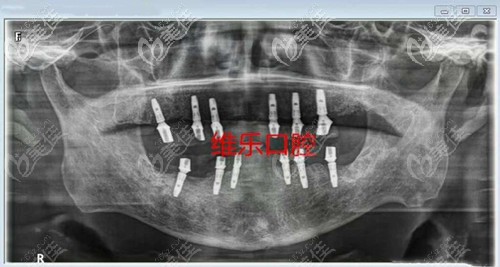

喏,牙齒種植后醫(yī)生拍片就是這樣的

從拍片可以看出我醫(yī)生這個牙齒種植體的位置還是穩(wěn)固的,而且爺爺?shù)难例l也好了挺多的。